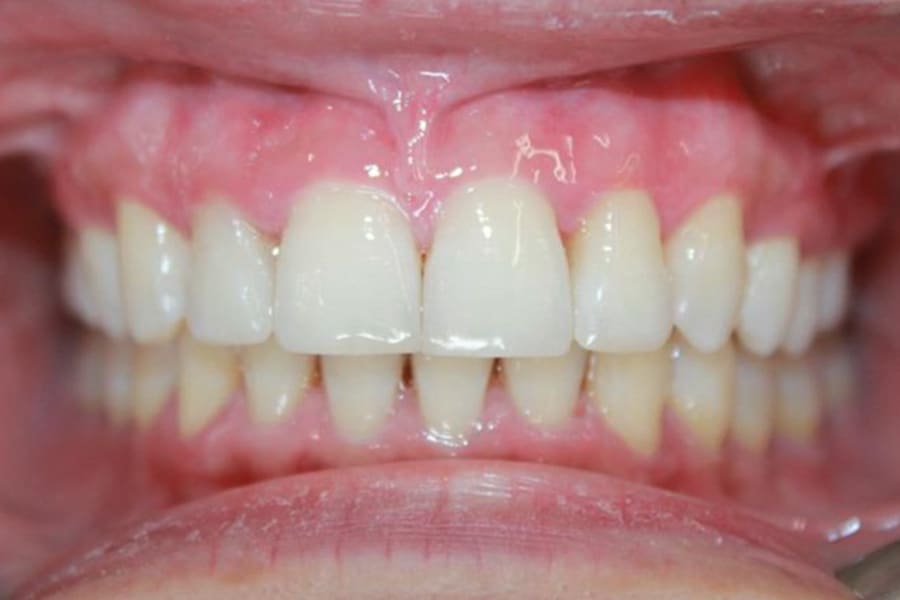

A 35-year-old woman presented with concerns of crowding, bruxism, and bite misalignment, which were associated with a class II malocclusion that would require a combination treatment of expansion, distalization, and molar derotation. ClearCorrect® aligner therapy (Straumann, clearcorrect.com) was selected as the primary modality, as the patient requested a non-invasive, esthetic treatment. The treatment plan was designed to be completed within 6 months of active aligner therapy. Class II elastics were prescribed, and the ClearCorrect FLEX case plan was chosen to allow for refinements, as needed. After comprehensive digital records were taken, the first set of aligners was delivered, engagers were bonded, and the patient was instructed to wear aligners on a 14-day cycle with full-time class II elastic wear. To enhance efficiency, more engagers were placed, including posterior attachments, to maximize control over molar distalization and anchorage. Interproximal reduction of 0.3 mm was performed in a few contacts at the initial appointment to facilitate space closure and alignment. Due to the complexity of the correction and the patient’s history of bruxism, a lower 3-3 bonded retainer was placed, and retainers were fabricated for both arches. The patient expressed a high level of satisfaction with the ClearCorrect aligner therapy, noting the comfort and esthetics of the aligners and the ability to achieve a fully corrected class II occlusion in just 6 months of treatment.